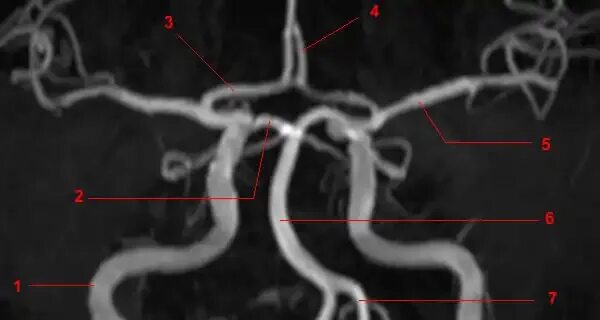

Сегменты вса мрт